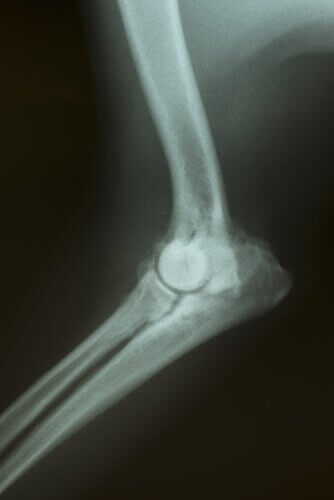

Dessa forma, exames de sangue, raios-x, ultrassonografias, tomogramas, entre outros, podem ser realizados.